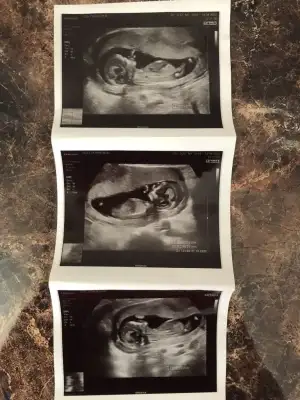

kız gibi duruyor canım 7 haftalık görüntüsü var mı?Merhabalar, benim bebeğimin de cinsiyetini söyleyebilir misiniz? 9+3 karından ultrason

Evet bu da 7 haftalık görüntüsü.kız gibi duruyor canım 7 haftalık görüntüsü var mı?